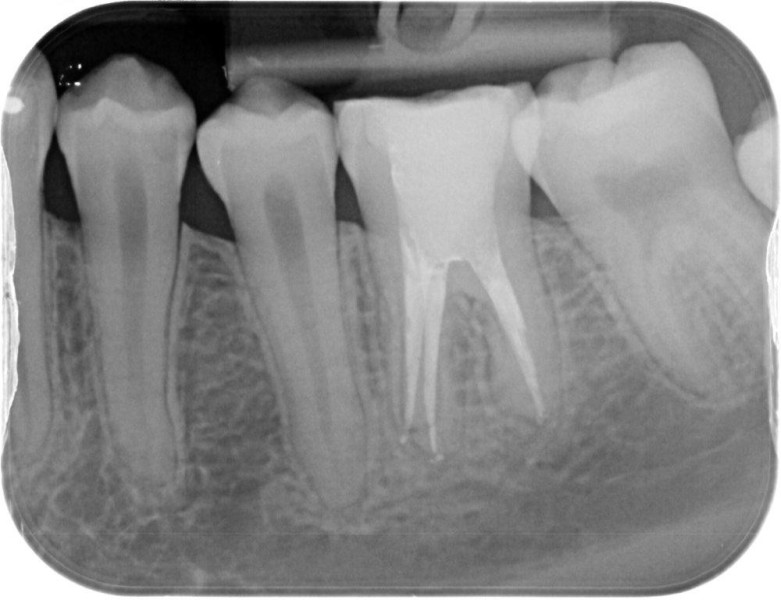

Premolar retreatment